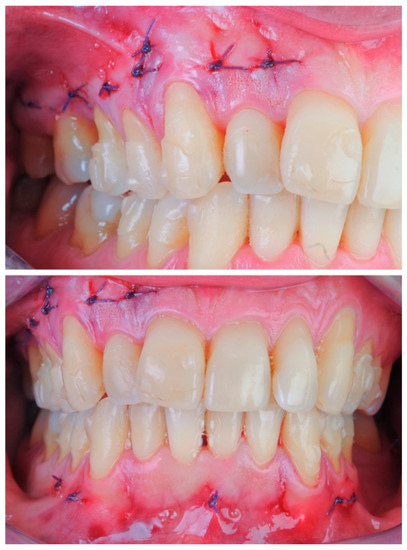

2.3.1. Example—Anterior Open-bite